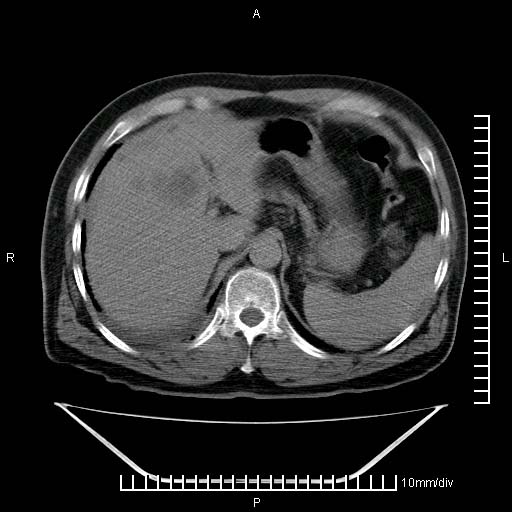

标题: CT25082:肝脏增强:男性,70岁 [打印本页]

标题: CT25082:肝脏增强:男性,70岁

患者以心脏疾病收住院,腹部无明显症状,b超查肝脏有占位。

增强效果不理想。考虑转移,胆囊壁明显增厚,不排除胆囊癌肝转移。

病灶无强化,考虑囊肿。

牛眼征,中心坏死无强化,外缘强化,最外缘又见低密度,考虑转移,与脓肿鉴别

肝内多发转移瘤,右下肺炎症并少量胸水。胃壁增厚建议胃镜,胰尾部“病变”为肠管。

1)肝脏多发性转移瘤(不排除胰尾癌转移所致可能)。2)腹水。3)右侧少量胸腔积液。

ct25082 结果:转移瘤

外院mr结果:胰尾恶性占位。